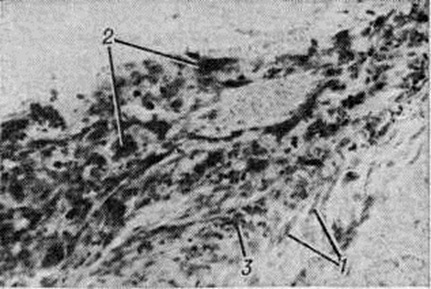

ПахименингитПахименингит (pachymeningitis; греческий pachys толстый, плотный + meninx, meningos оболочка + -itis) — воспаление твёрдой оболочки головного и спинного мозга. Воспалительный процесс твёрдой оболочки головного мозга называют церебральным пахименингитом, а твёрдой оболочки спинного мозга — спинальным пахименингитом. В зависимости от того, какие слои оболочки поражены, различают наружный, внутренний и внутри-оболочечный Пахименингит По характеру воспалительного процесса различают серозный, геморрагический и гнойный Пахименингит, по течению — острый и хронический Пахименингит Патологоанатомические изменения при серозном Пахименингит характеризуются разрыхлением, отёком и резким полнокровием твёрдой оболочки головного и спинного мозга. При геморрагическом внутреннем Пахименингит в патологический процесс вовлекается твёрдая оболочка головного мозга, чаще верхнелатеральной поверхности лобной и височной долей полушария головного мозга, иногда обоих полушарий мозжечка, реже области турецкого седла. В твёрдой оболочке спинного мозга геморрагический внутренний Пахименингит встречается крайне редко. При этой форме происходит геморрагическое пропитывание или расслоение твёрдой оболочки головного мозга вследствие разрыва стенок или флебита мозговых вен в зоне впадения их в синусы твёрдой мозговой оболочки. Макроскопически поражённая оболочка имеет пёстрый вид за счёт чередования буровато-коричневых старых очагов и скопления крови в образующихся в результате повторных кровоизлияний полостях (цветной рисунок 4). В дальнейшем содержимое полостей полностью обесцвечивается и образуются так называемый гигромы твёрдой оболочки головного мозга. Микроскопически при геморрагическом Пахименингит обнаруживаются очаги кровоизлияний разной давности и полости, внутренняя поверхность которых выстлана эндотелием (рисунок 1). Организация геморрагических масс (смотри полный свод знаний: Организация в патологии) происходит путём врастания в них грануляционной ткани с образованием тонкостенных сосудов (рисунок 2). В грануляционной ткани выявляются скопления гемолизированной крови и отложения гемосидерина; в формирующейся фиброзной капсуле отмечается пролиферация макрофагов (рисунок 3). Капсула может быть инфильтрирована лимфоидными и плазматическими клетками. Особенностью геморрагического Пахименингит является медленное развитие процессов организации и недостаточно выраженное свёртывание излившейся крови вследствие малого содержания в ней фибрина или примеси цереброспинальной жидкости. В центральных отделах полостей процессы организации могут развиваться быстрее, что сопровождается в ряде случаев отложением солей кальция или окостенением твёрдой оболочки головного мозга. При гнойном Пахименингит твёрдая оболочка головного и спинного мозга полнокровна, гнойный или фибринозно-гнойный экссудат располагается на наружной поверхности оболочки или в субдуральном пространстве, постепенно подвергаясь организации и отграничению спайками; при этом образуются экстра или субдуральные абсцессы. Микроскопически в твёрдой оболочке головного и спинного мозга обнаруживаются периваскулярные инфильтраты из сегментоядерных лейкоцитов и грануляционная ткань разной степени зрелости. При стихании процесса развивается фиброз оболочки. При хронический Пахименингит развивается фиброз твёрдой оболочки головного и спинного мозга и происходит сращение её с окружающими тканями. Распространение процесса по протяжению твёрдой оболочки спинного мозга способствует образованию муфтообразного утолщения с последующим сдавлением корешков спинномозговых нервов и их атрофией. При туберкулёзе, сифилисе, актиномикозе и других хронический инфекциях встречается хронический гиперпластический Пахименингит. Твёрдая оболочка спинного мозга при этом утолщена за счёт пропитывания желатинозным экссудатом, имеет желтовато-серый цвет, может быть сращена с окружающими тканями. Микроскопически обнаруживаются специфические гранулемы, при сифилисе преобладают гуммозные поражения. Церебральный пахименингит. Различают несколько форм церебрального Пахименингит: серозный церебральный Пахименингит, геморрагический внутренний и внутридуральный Пахименингит, наружный и внутренний гнойный церебральный Пахименингит |